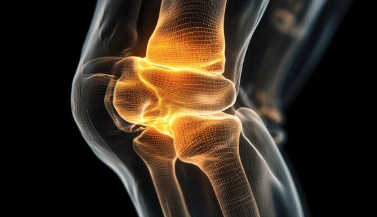

오금(슬와부)은 무릎 뒤쪽에 위치한 부위로, 인대, 근육, 신경 등이 복잡하게 얽혀 있습니다.

이 부위에서 통증이 발생하면 걷기, 계단 오르기, 무릎을 구부렸다 펼 때 불편함을 유발할 수 있습니다.